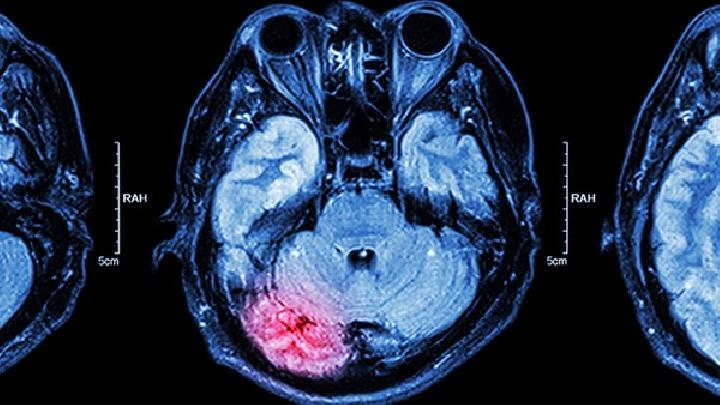

脑供血不足典型症状都有哪些?对于脑供血不足这个疾病大家都不陌生,而且这个疾病的发病率在不断的增高,很多的年轻人都开始患有脑供血不足,那么,下面我们就一起了解下脑供血不足典型症状都有哪些吧。

要原因是:因为颈椎寰枢关节和颈5颈6关节错位,刺激椎动脉引起动脉血管腔狭窄或血管痉挛,通过的血流量减少,致使所供应的脑区发生供血不足。

脑供血不足可能由动脉粥样硬化、高血压、颈椎退行性变、心脏泵血功能下降等原因引起,常见表现为头晕、记忆力减退、视物...

脑供血不足可能由颈椎病、动脉粥样硬化、高血压、心脏疾病等原因引起。 1、颈椎病 颈椎退行性病变压迫椎动脉,导致椎...